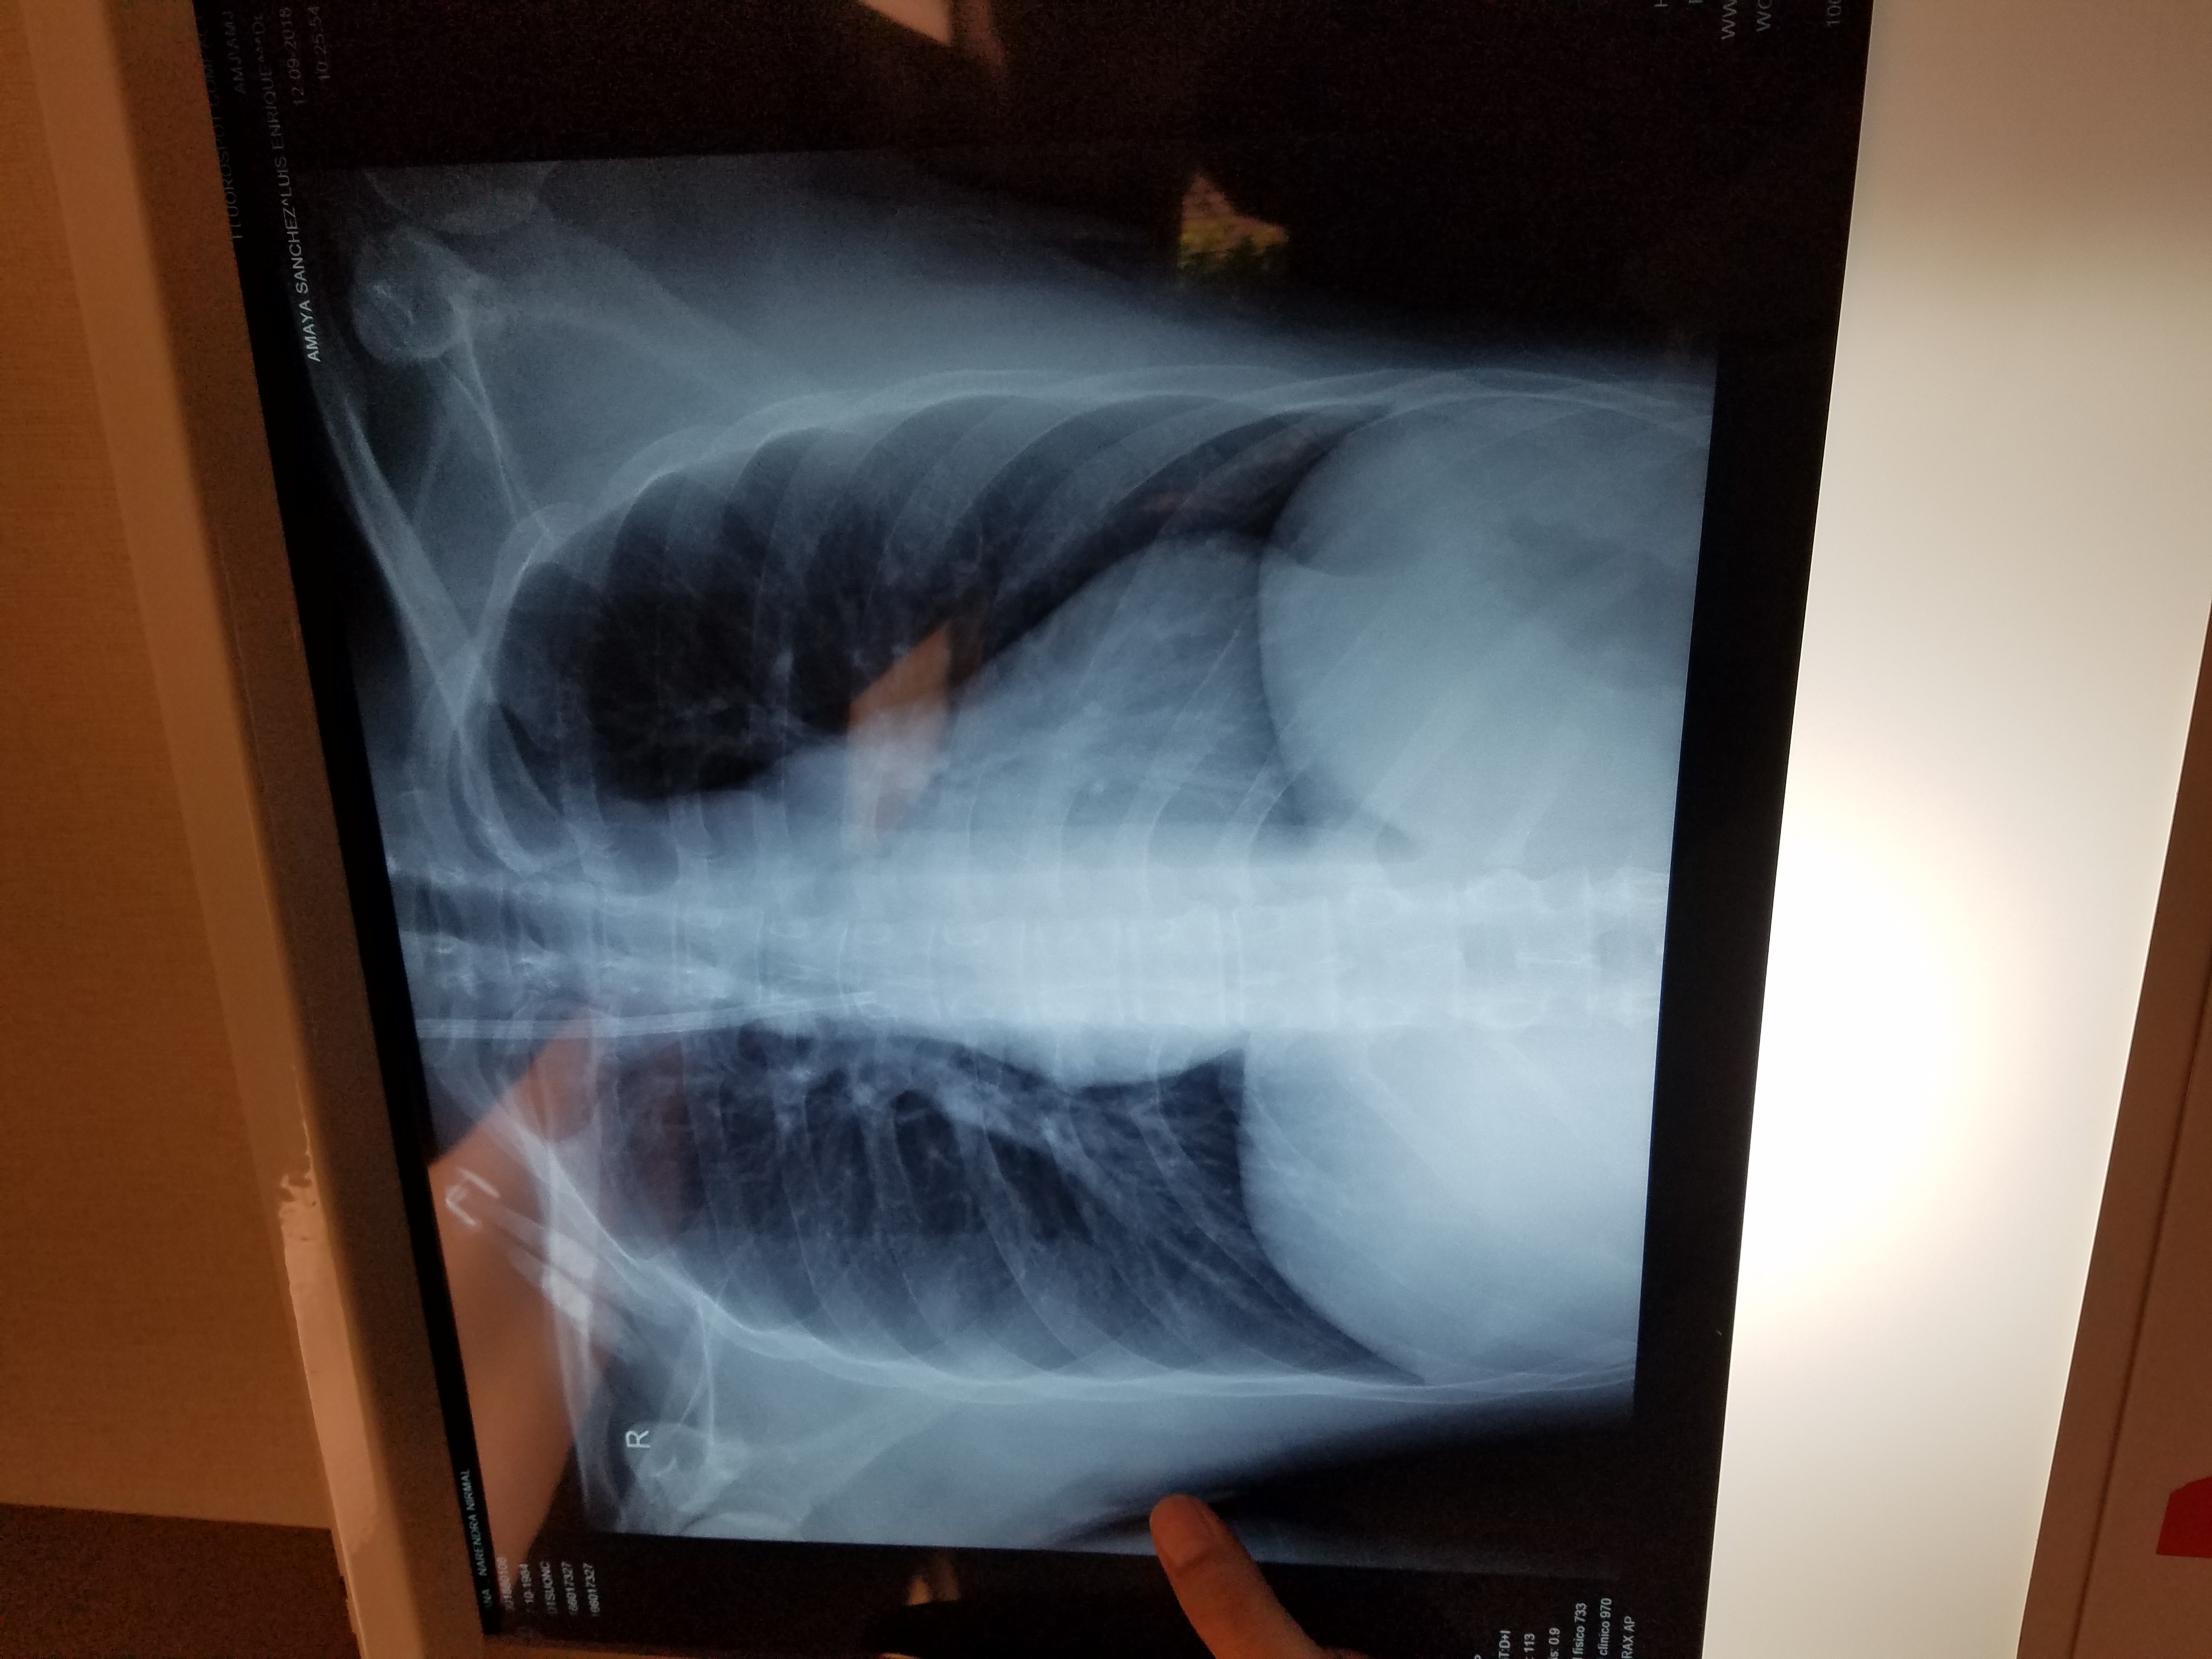

20180912_104607.jpg